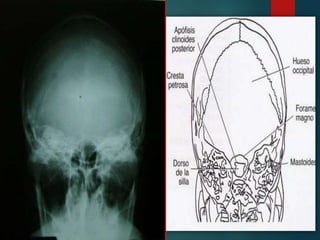

Este documento proporciona instrucciones para realizar diferentes proyecciones radiográficas del cráneo, incluyendo las proyecciones anteroposterior (AP), submentovertex (SMV), parietoorbitaria y transorbitaria de Guillen. Describe los ángulos y posiciones requeridos para cada proyección y las estructuras óseas que deberían ser visibles en cada imagen resultante.